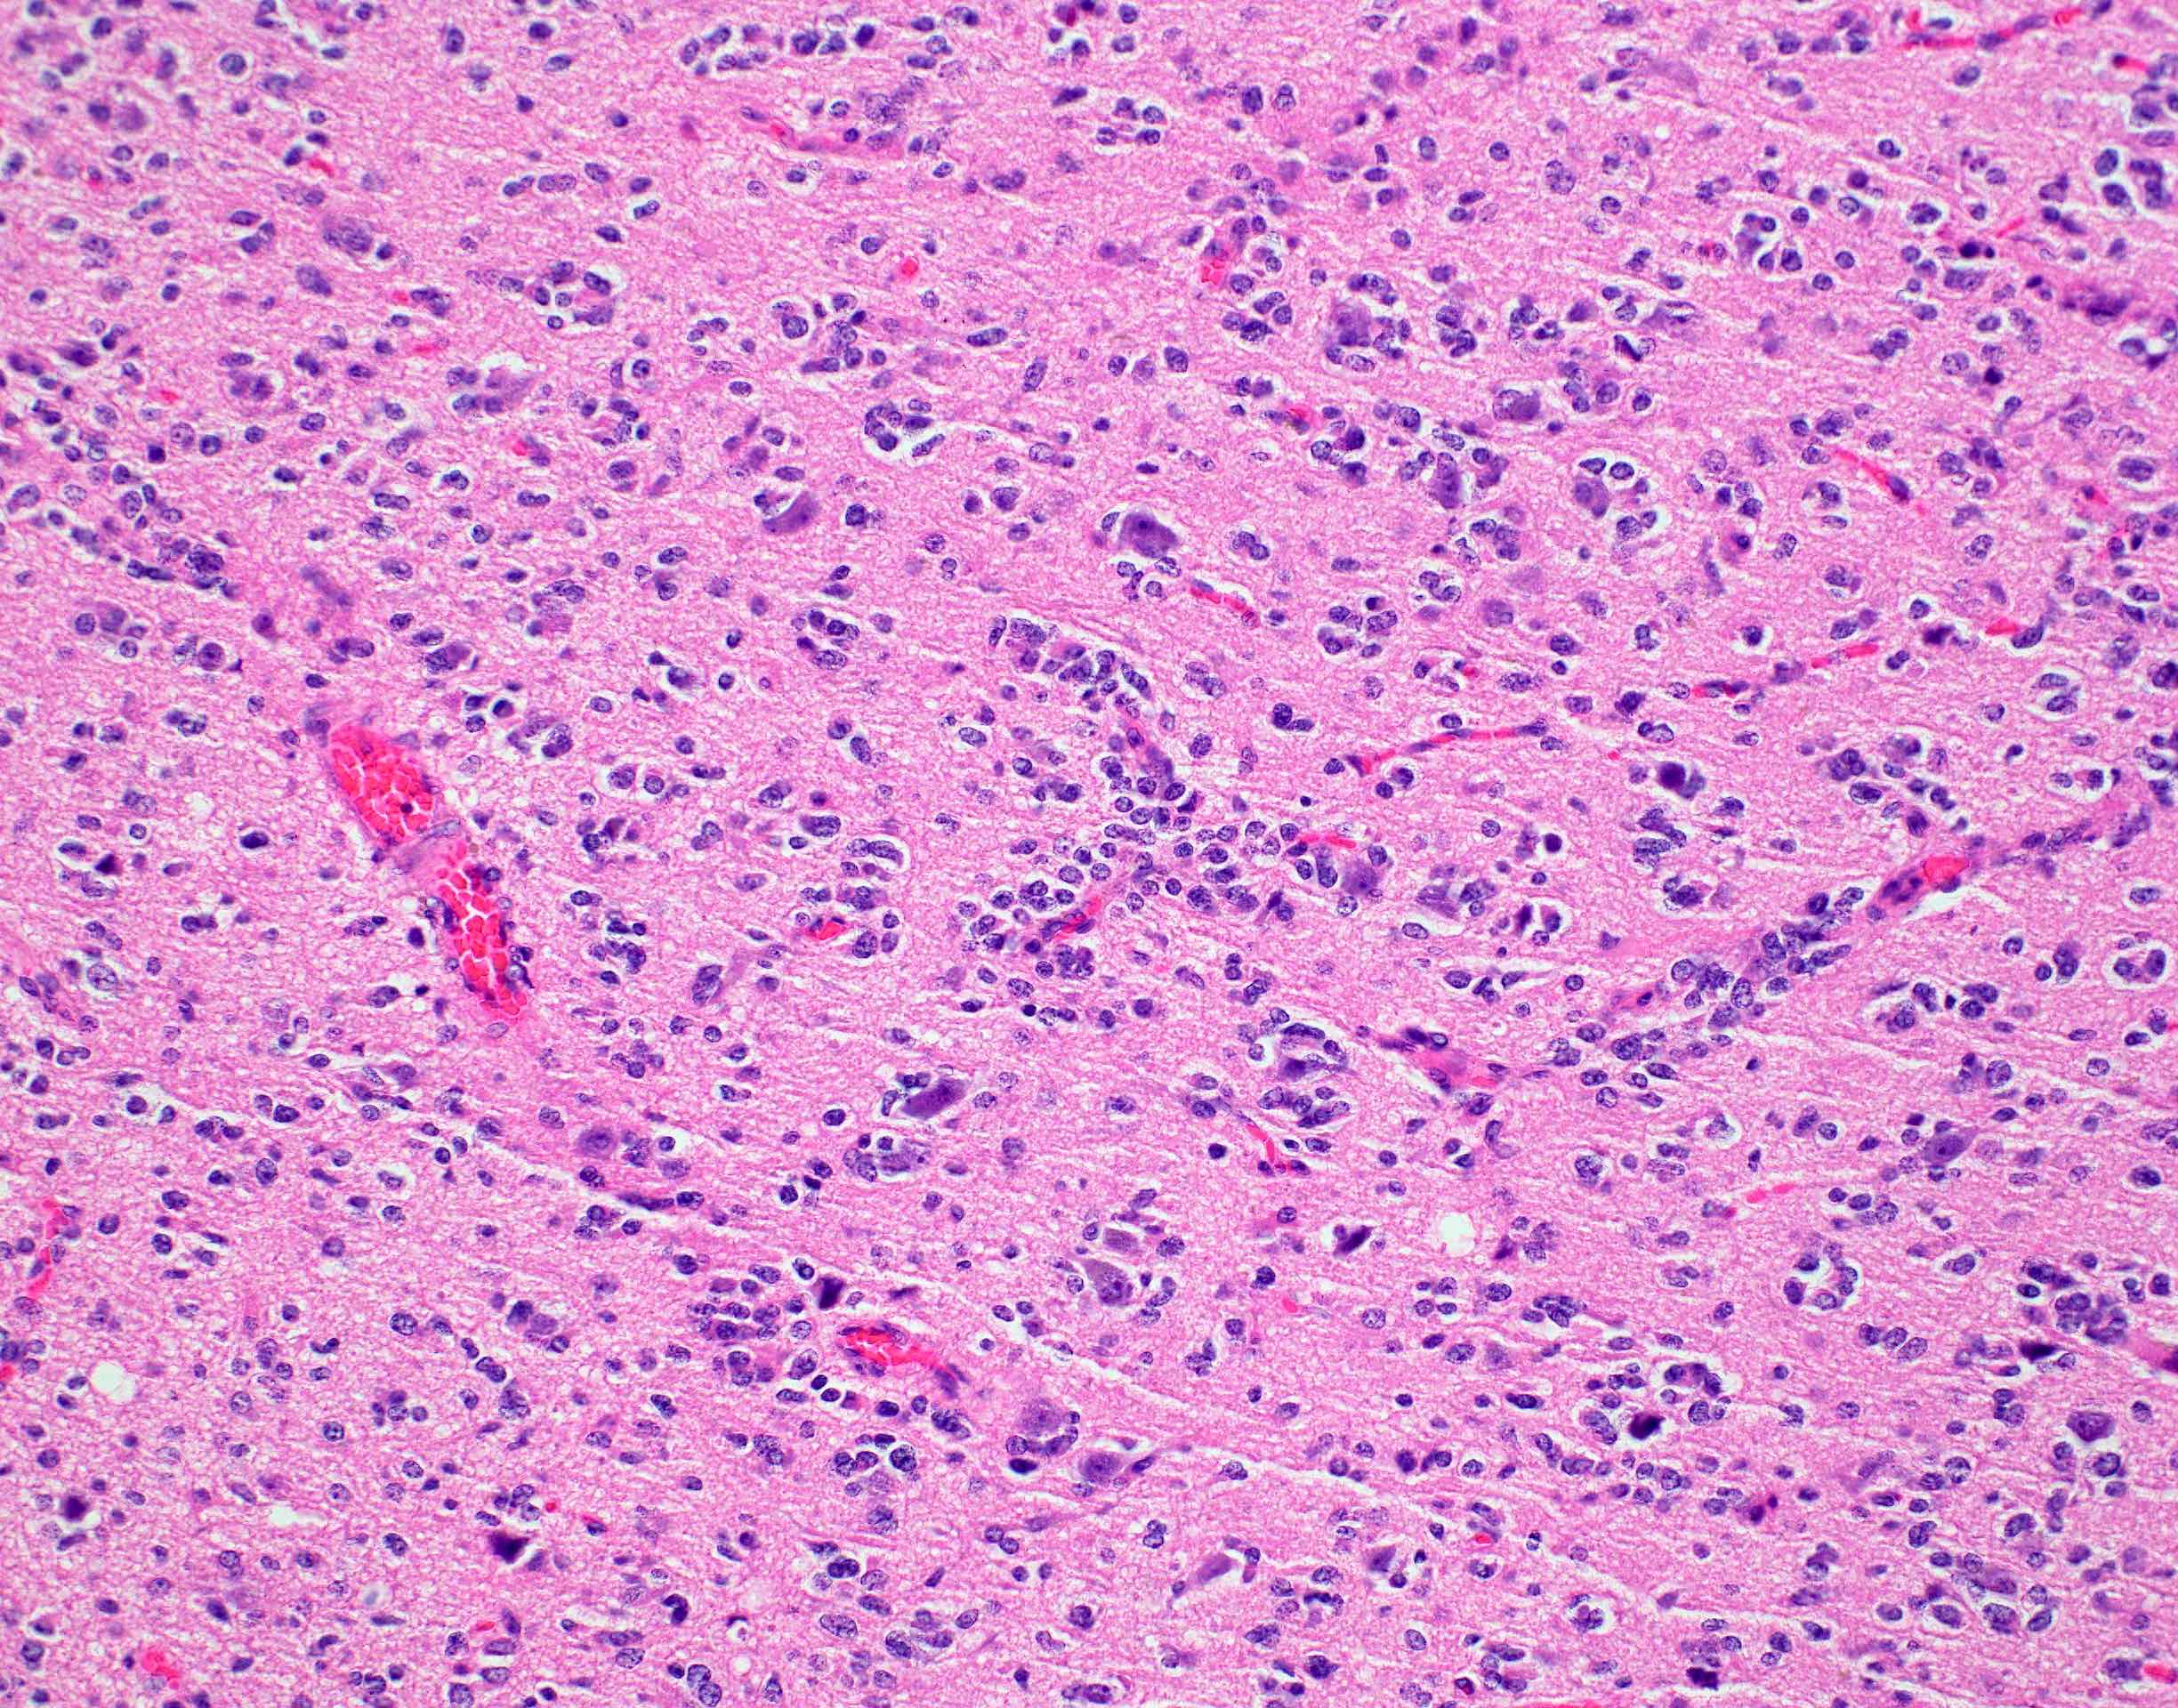

Microscopic (histologic) description

- Closely packed cells with small, round, monotonous nuclei (slightly larger than a normal oligodendrocyte)

- Perinuclear clearing (fried egg appearance)

- Formalin fixation artifact

- Will not be seen on frozen sections or smear preparations

- Network of thin walled, branching blood vessels (chicken wire vasculature)

- Microcalcifications (calcospherites) are characteristic

- Presence of perineural, perivascular or subpial aggregates of tumor cells (secondary structures of Scherer)

- Occasional mitoses and moderate nuclear atypia are still consistent with grade 2 designation (J Neuropathol Exp Neurol 2001;60:248)

- Not uncommon to find well differentiated / fibrillary astrocytic morphology (Acta Neuropathol 1984;64:265)

- Features of CNS WHO grade 3 oligodendroglioma:

- Presence of microvascular proliferation

- Presence of necrosis

- Presence of brisk mitotic activity

- Strict mitotic figure cutoffs do not currently exist; some authors suggest ≥ 6 mitoses per 10 high power fields for WHO grade 3 designation in tumors without necrosis or vascular proliferation (Neuro Oncol 2014;16:1244, Neuro Oncol 2016;18:888)

Microscopic (histologic) images

Contributed by Jared T. Ahrendsen, M.D., Ph.D. and John DeWitt, M.D., Ph.D.